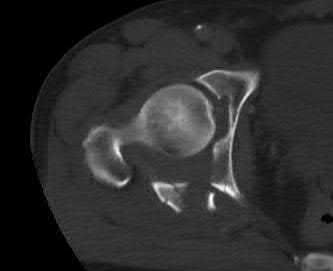

A 12-year-old obese boy presents with vague left thigh and knee pain. He is diagnosed with a Slipped Capital Femoral Epiphysis (SCFE) as seen in similar clinical scenarios. During percutaneous in-situ fixation, unrecognized penetration of the guide wire into the hip joint occurs. What is the most likely specific complication resulting from this technical error?

Chondrolysis is a severe complication of SCFE characterized by rapid destruction of the articular cartilage. While it can occur idiopathically, its most established iatrogenic cause is unrecognized intra-articular hardware penetration. The 'approach-withdraw' fluoroscopic technique is required during pinning to assure pins are entirely intraosseous. Avascular necrosis (AVN) is usually due to damage to the epiphyseal blood supply (retinacular vessels) secondary to the initial displacement, forceful closed reduction, or posterosuperior pin placement.